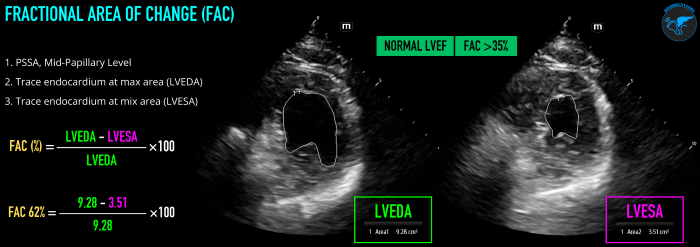

FAC measures the change in left ventricular area between diastole and systole to estimate LVEF. The operator will first obtain a PSSA view at the mid-papillary level. Freeze the image on screen, and scroll through to find the maximum area (left ventricle end diastolic area, LVEDA) and the minimum area (left ventricle end systolic area, LVESA). At each of these points, trace around the endocardial border of the LV, ensuring not to include the myocardium or papillary muscles. FAC% = (LVEDA - LVESA)/LVEDA x 100 (Figure 4). Like FS, FAC measures a change in area/distance and does not result in a value that is the LVEF, which is a measure of volume. LVEF can be estimated based on the FAC% value.10 Regional wall motion abnormalities, preload, and afterload can significantly influence FAC.

LVSF_Figure 4_Fractional Area of Change v2.pngFigure 4. Fractional Area of Change (FAC) technique and normal values visual guide.